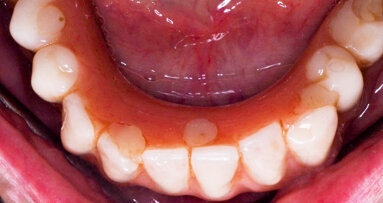

Third milestone of the peri-implantitis prevention is Supportive Periodontal Therapy (SPT): the lack of a regular and effective SPT is a risk factor for the development of peri-implantitis.21 Every recall should be accompanied by a proper examination and probing13 to detect and effectively treat any case of peri-implant mucositis, since it can early progress to peri-implantitis.14 Sometimes it might be necessary to remove the overlying prostheses in order to achieve a more effective treatment and, in some cases, a better resolution of the inflammatory disease. (Fig.5,6)

Fig.5: Implant bar with abundant plaque deposits and evident mucositis.

Fig.6: Resolution of mucositis after non-surgical therapy and healing period without bar.